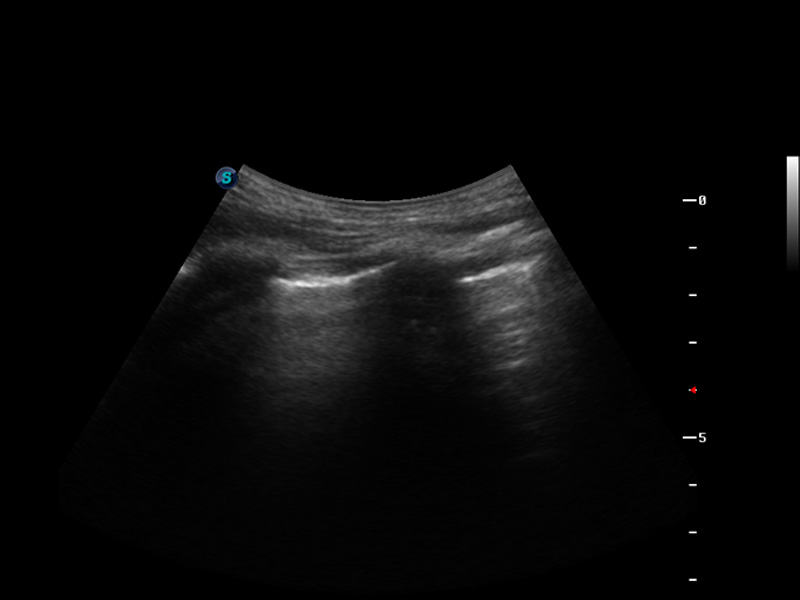

S9便携式彩色多普勒超声诊断仪是乐玩lewin国际研发的高端便携彩超设备,外观设计新颖、产品性能卓越。S9在便携超声领域采用了突破传统的触摸屏交互设计,并以先进的软件硬件技术和设计理念,为您带来清晰的图像质量、稳定的工作性能和便捷的操作体验。

μ-Scan微米成像